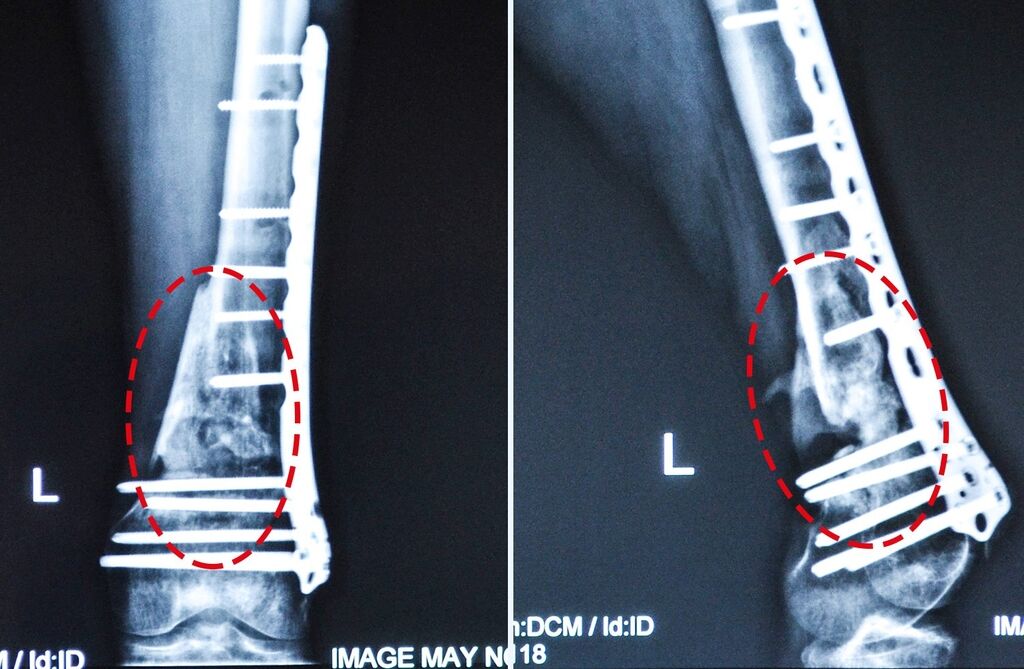

Першу допомогу чоловіку надали у с. Кримське, потім доправили у Харківський військовий шпиталь, де на ногу встановили апарат Ілізарова, а в травні 2015 року у Київському центральному клінічному шпиталі зламану кістку зафіксували пластиною (виконали остеосинтез).

Сергій переніс уже 7 операцій на нозі, але за рік, який минув із часу останнього хірургічного втручання, кістки так і не зрослися. Наразі через порушений кровообіг м’язи ноги зсохлися і вкоротилися, від чого нога та пальці повністю не розгинаються.

Ліва нога:

– незрощений після металоостеосинтезу надвиростковий перелом лівої стегнової кістки,

– вкорочення кінцівки до 4 см,

– посттравматичне пошкодження малогомілкового нерву,

– ішемічна контрактура лівої стопи з молоткоподібними пальцями.